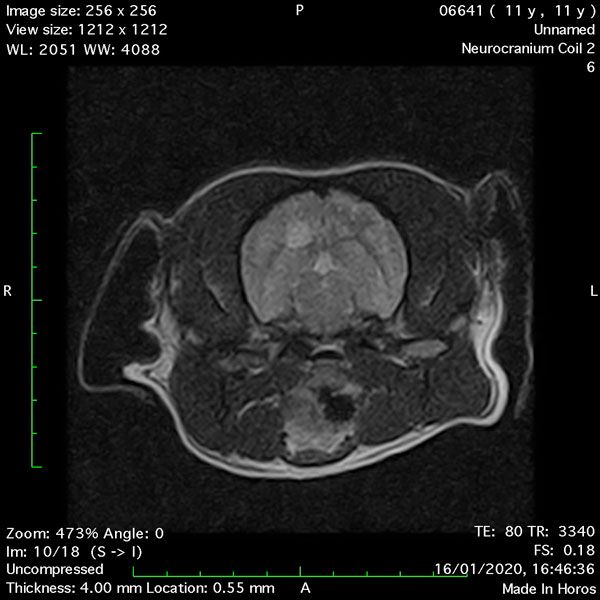

- Transverse T2 – Turbo Spin Echo-S (contrast administered slowly during this sequence) (Figure 2) (Figure 3);

MRI images were viewed in DICOM format (Digital Imaging and Communications in Medicine) (Figures 1-7) and assessed in-house under the guidance of a board-certified radiologist. The series were evaluated for changes in intensity in the T1- and T2-weighted sequences (T1w and T2w, respectively). There was a 4mm x 7mm x 7mm intra-axial, wedge-shaped hyperintense reasonably-well demarcated region in the right cerebrum visible in the T2w images (Figures 2-3). This was consistent with a focal infarct. No contrast enhancement, anatomical abnormality nor space occupying lesion was noted in the T1w sequences (Figure 1, Figure 4). There was no observed pathology on assessment of the FLAIR images (Figure 5).

Figures 1-7: Images obtained with MRI depicted in sequential order and assessed under the guidance of a board-certified radiologist in-house.